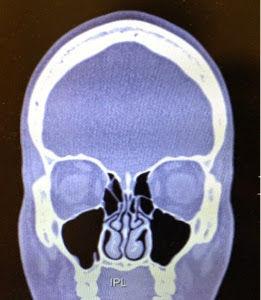

The good news is I'm back in the tiny room now, and my CT scan shows that there's a kitty face inside my skull. I suspected that all along... Do you see it?? I can't not see it.

I'm here to find out if I can continue scuba diving and stop getting horrible ear infections all the time. He's going to tell me I need surgery, which is no bueno...